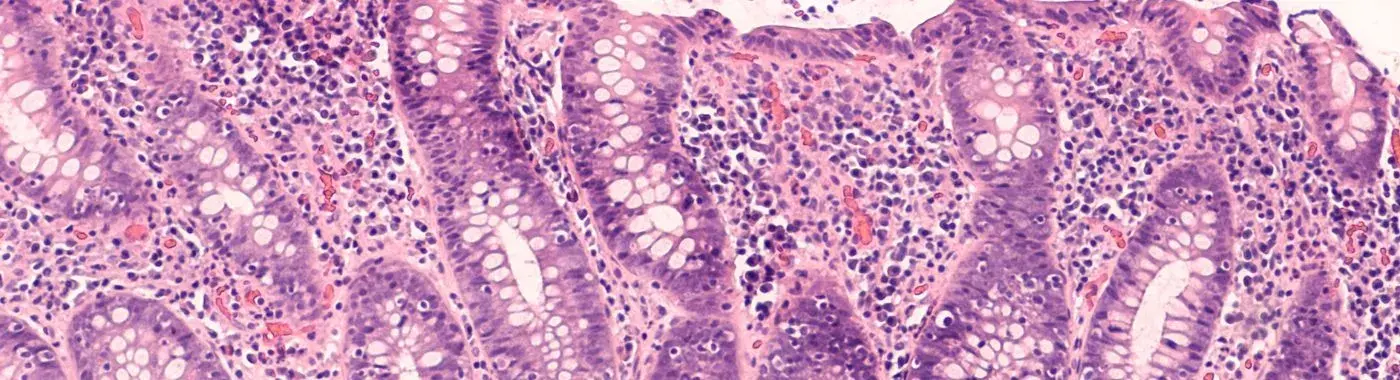

Lymphocytic colitis is a form of microscopic colitis, a condition that causes inflammation of the colon without visible lesions during standard endoscopic examinations. It is characterized by an increase in lymphocytes, a type of white blood cell, in the colon's mucosal layer. This condition leads to chronic, non-bloody diarrhea, abdominal pain, and other gastrointestinal symptoms. Unlike other forms of colitis, lymphocytic colitis does not typically result in significant weight loss or malnutrition, but it can still cause considerable discomfort and distress.

• Biopsy: Tissue samples taken during a colonoscopy are examined under a microscope to check for an increased number of lymphocytes in the colon's mucosal layer.